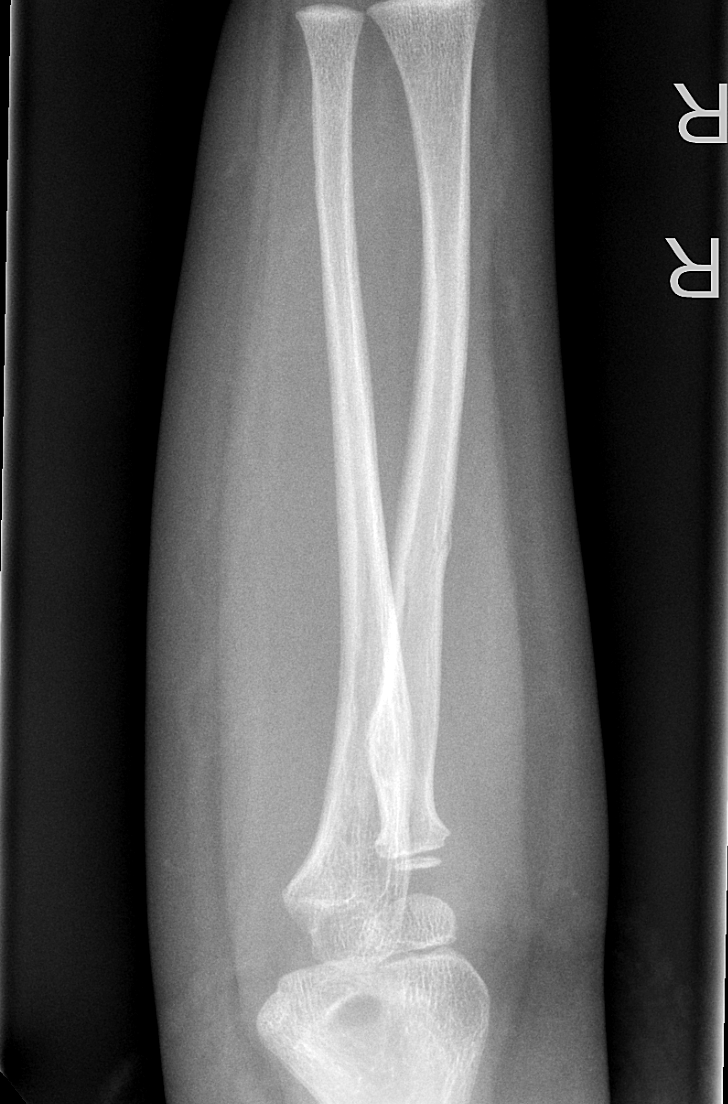

Info Images Findings Impression Reco/Acuity Case Images View Images / Launch Visage Case Notes History 2-month-old presents with decreased right arm movement, increased fussiness, and increased sleepiness for 2 days. Suspected non-accidental trauma. Exam Skeletal survey Prior Study none Dicom View Reference Material

Section 1 Submit Findings CB1550 Findings Skeletal Survey - Technique Check Skull AP/Lat Yes No Cervical and Thoracolumbar spine Yes No Chest X-Ray Yes No Ribs – Left/Right Oblique Yes No Abdominal X-Ray Yes No Pelvis with both hips Yes No Bilateral Humerus, Forearm, Hand Yes No Bilateral Femur, Tibia/fibula, feet Yes No Any additional lateral views of the extremities Yes No The exam is over or under penetrated. Yes No The exam may or may not be limited by overlying structures or soft tissues, body habitus, patient positioning, support devices, or motion. Yes No The area of concern is indicated by the patient, technologist, or care provider. Yes No The area of concern is included on the exam. Yes No Soft Tissues There is soft tissue swelling, indistinctness of fat/muscle planes, gas, or laceration in the area of clinical concern. Yes No There is an effusion, fat pad displacement, or fat fluid level. Yes No There is a radiodense or lucent foreign body. Yes No There are other densities, calcifications, post-surgical changes, or support devices in the soft tissues. Yes No Any support lines/tubes. Yes No Bone There is a break or interruption of the continuity of the cortical or cancellous bone. Yes No There is overriding of the trabeculae with apparent sclerosis. Yes No There is displacement of a fracture fragment. Yes No There is bowing of the bone in addition to the fracture at the apex of the bowed bone concerning for the greenstick. Yes No There is a spiral fracture of the leg concerning for toddler’s fracture. Yes No There is abnormal angulation or bulging of the cortical surface relative to the normal cortex which could be from a buckle or torus fracture. Yes No There is a displaced fragment which may be from avulsion by a tendon, ligament, or joint capsule or from a comminuted or other fracture. Yes No The stress trabeculae or other trabeculae of the cancellous bone are interrupted or otherwise abnormal. Yes No There is subperiosteal or endosteal reaction which could indicate a healing or subacute fracture or other abnormality. Yes No There is hard/soft callus formation. Yes No There is remodeling of the bone. Yes No There is a corner fracture or metaphyseal lesion that could be from nonaccidental trauma. Yes No There are multiple fractures of different ages. Yes No There are vertebral body/spinous process fractures. Yes No There are rib fractures. Location - posterior or lateral. Yes No There is scapular/sternal fracture. Yes No There are fractures of the digits. Yes No There are wormian bones. Yes No There are intrasutural bones. Yes No There is metaphyseal abnormality (lucencies, increased density, erosion) which may be from something other than injury such as stress, metabolic disease (e.g. rickets with loss or distortion of the zone of the provisional calcification), neoplasm (e.g. leukemia), heavy metals, inflammation, or infection. Yes No There are metaphyseal spurs. Yes No There are bony deformities involving multiple bones. Yes No The bones are gracile. Yes No There are non-healing fractures. Yes No There is/are focal or multifocal lytic/lucent, blastic/sclerotic or mixed density lesion(s) or other abnormality. Yes No Overall bone density is increased or decreased with or without thinning or thickening of the cortical or cancellous bone. Yes No Growth plates, ossification centers, apophyses The growth plate(s) is/are abnormal. Yes No There is widening of the physis from a fracture with or without displacement of the epiphysis (Salter-Harris I). Yes No There is a fracture through the physis which then extends into the metaphysis with or without angulation or displacement (S-H II). Yes No There is a fracture through the physis which then extends into the epiphysis and is intra-articular, with or without angulation or displacement (S-H III). Yes No There is a fracture through the metaphysis, physis, and epiphysis which extends into the joint space with or without angulation or displacement (S-H IV). Yes No There is narrowing of the physis from a compression fracture (S-H V). Yes No The apophysis, epicondyle, secondary ossification center, or accessory ossicle is displaced or otherwise abnormal. Yes No The ossification centers are underdeveloped. Yes No Joints and alignment There is an effusion, fat pad displacement, or fat fluid level. Yes No The epiphysis or subchondral bone is fractured, interrupted, flattened, compressed, impacted, displaced, or otherwise abnormal. Yes No There is an intra-articular loose body or chondrocalcinosis. Yes No The joint is widened, narrowed, dislocated, malaligned, or incongruent. Yes No There is pseudoarthrosis. Yes No Other findings There are developmental changes or other anatomic variants or other existing conditions that may or may not be contributing to symptoms which can or should be further evaluated non-emergently or are otherwise incidental. Yes No The remainder of the exam is abnormal for age. Yes No The lungs show focal airspace opacity. Yes No There is pneumothorax. Yes No There is organomegaly. Yes No There is intra-abdominal calcification. Yes No There is displacement of the bowel loops. Yes No There is free intraperitoneal air. Yes No The bowel loops are dilated/obstructed. Yes No There is paraspinal soft tissue abnormality. Yes No